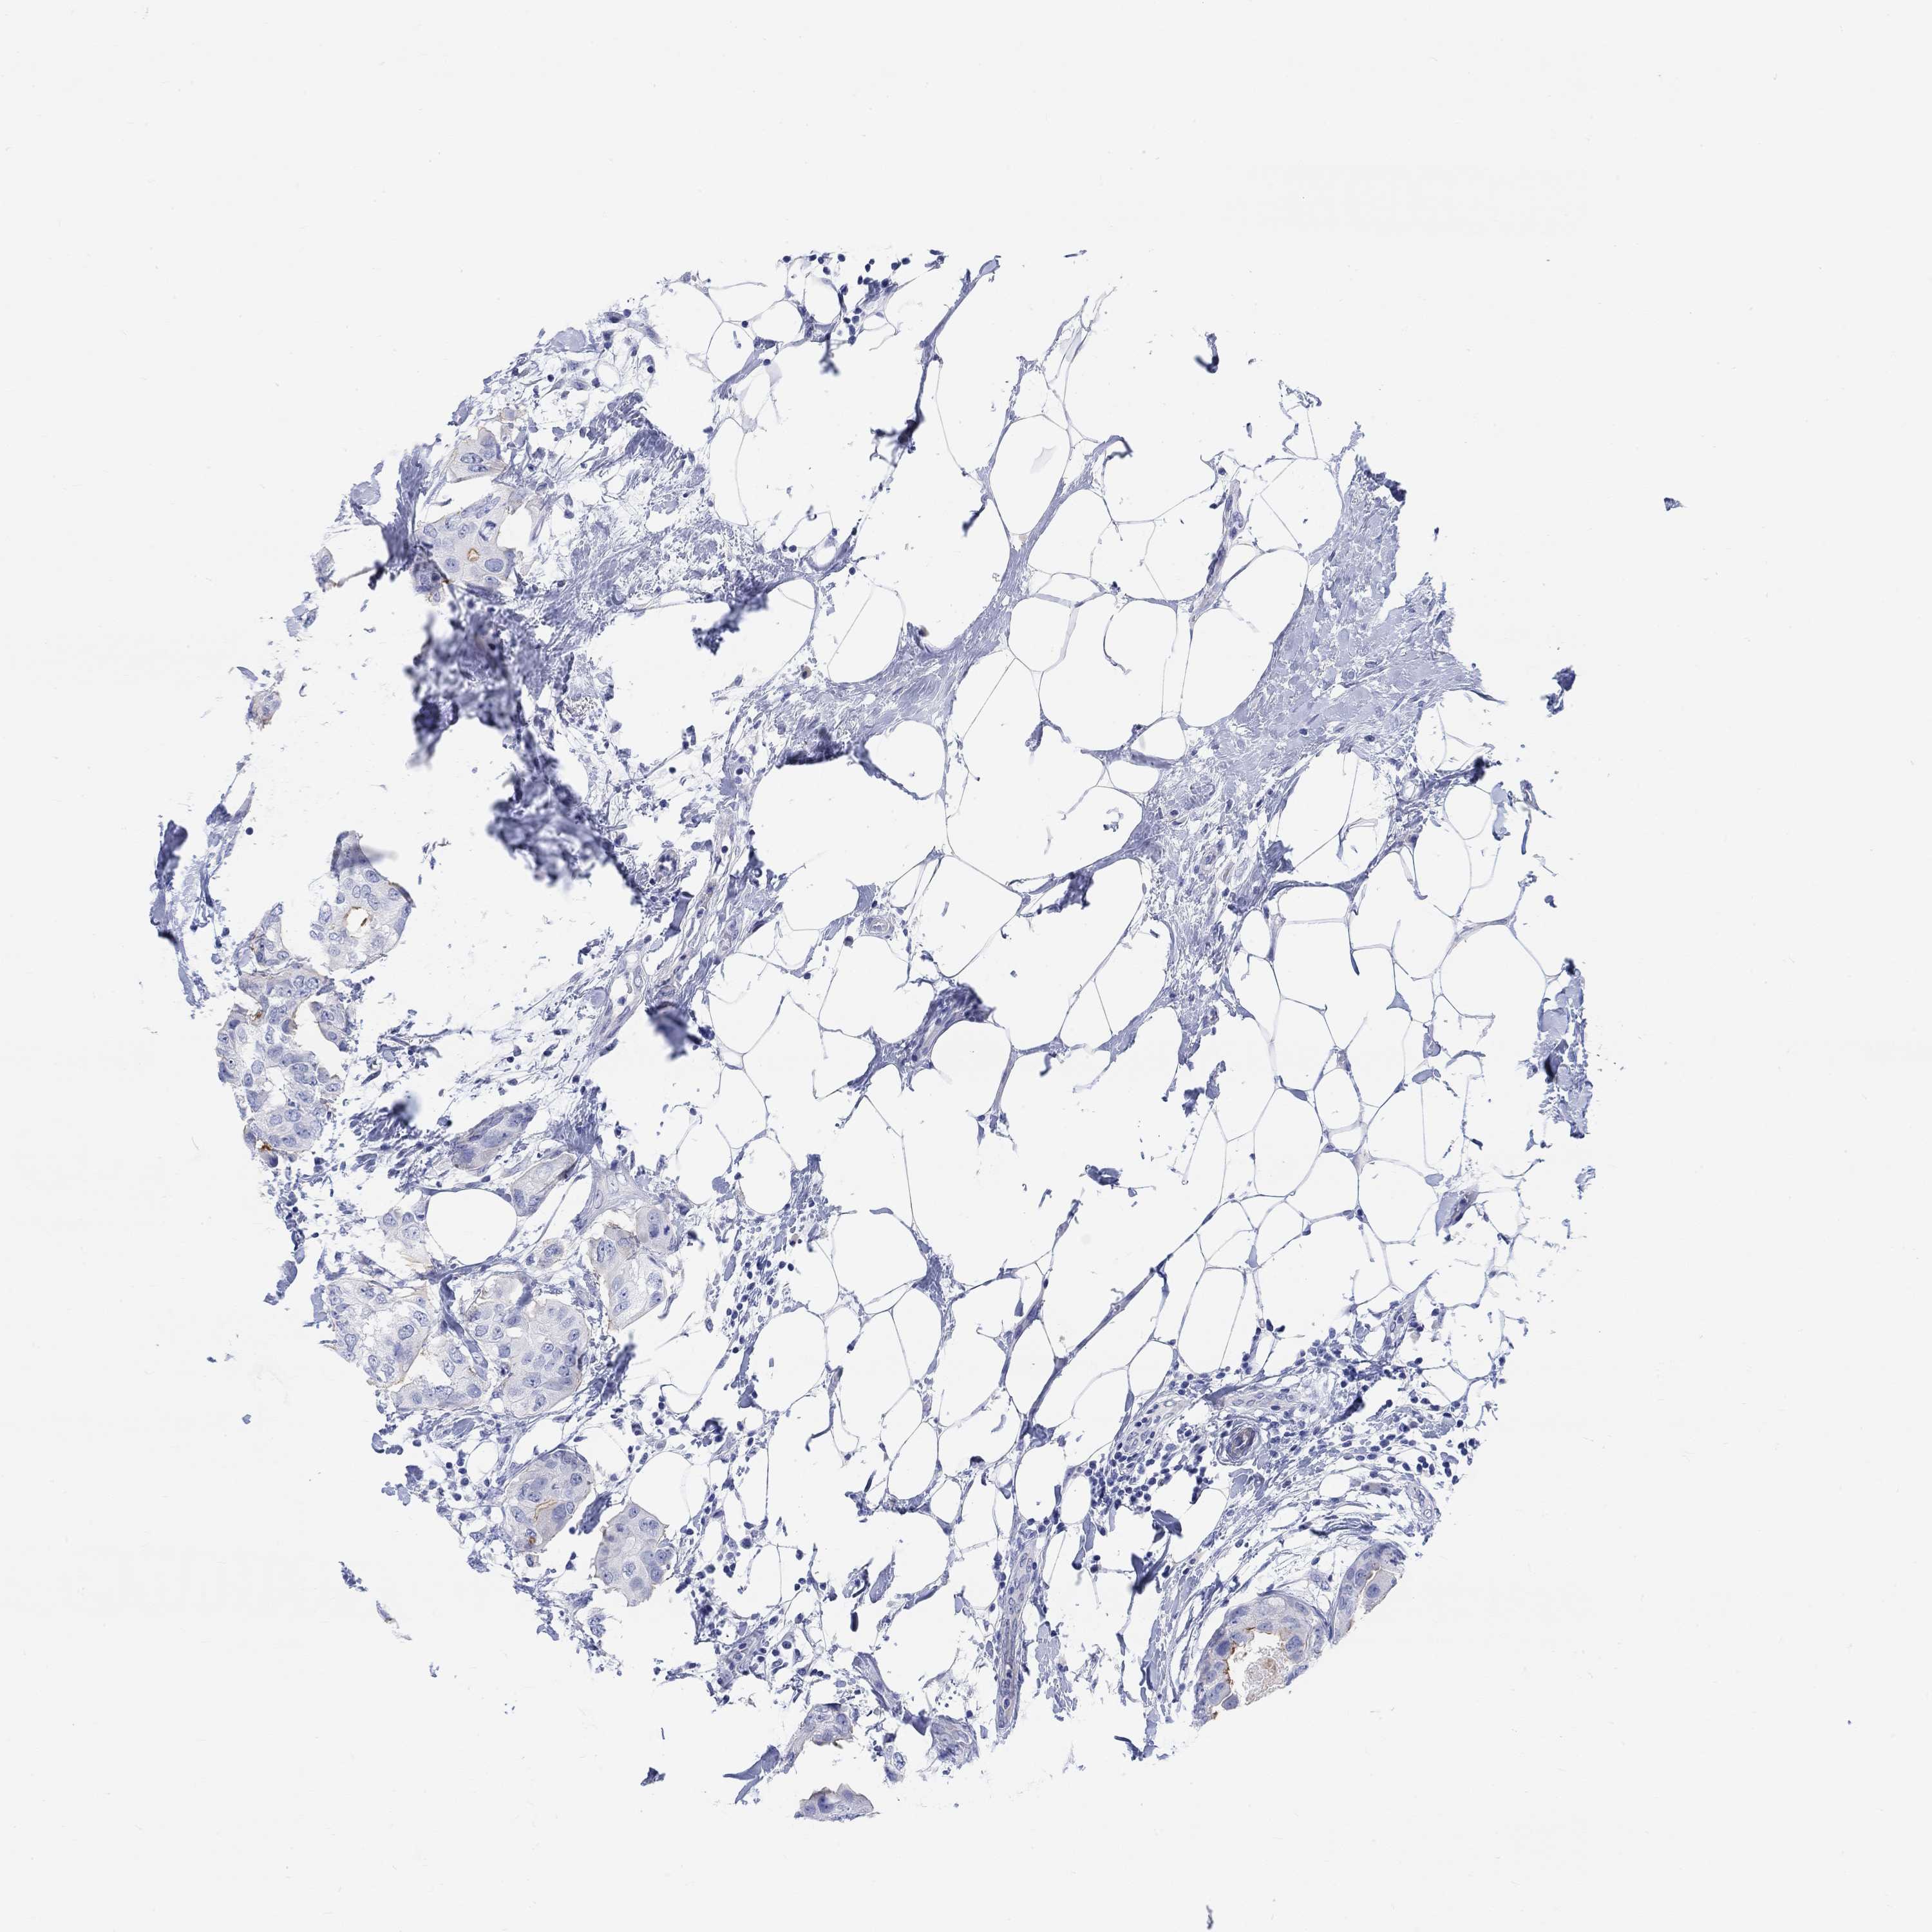

BRCA TCGA BRCA VALIDATION PROTEIN EXPRESSION